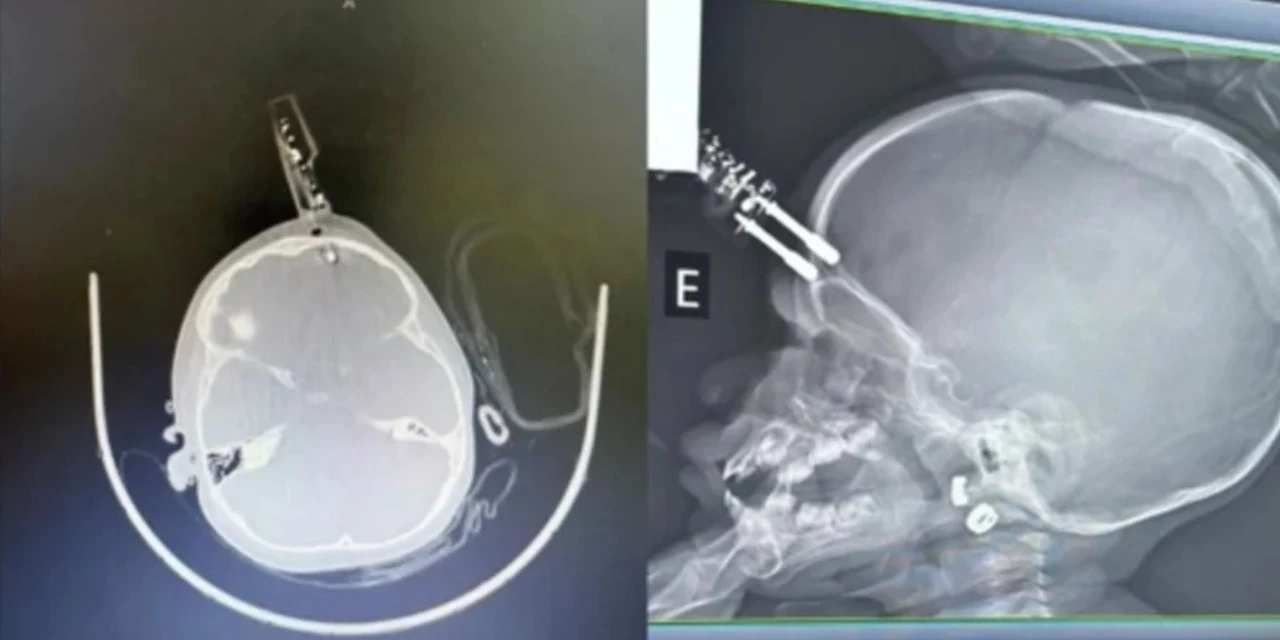

Uma menina, de apenas 1 ano, precisou passar por uma cirurgia de urgência na última terça-feira (13), após ficar com um carregador cravado em sua testa. O caso aconteceu no município de Divinópolis (MG), após a criança cair da cama.

De acrodo com informações do Metropoles, a mãe do bebê havia ido ao banheiro no momento do acidente. A criança estava com o carregador na mão quando caiu da cama, e acabou com o objeto cravado na cabeça.

A criança foi levada para a sala de cirurgias onde passou por procedimentos de limpeza, retirada do objeto, lavagem, fechamento e reconstrução da área atingida. De acordo com os médicos, a criança segue em observação e, até o momento, não apresenta sinais de sequelas neurológicas.